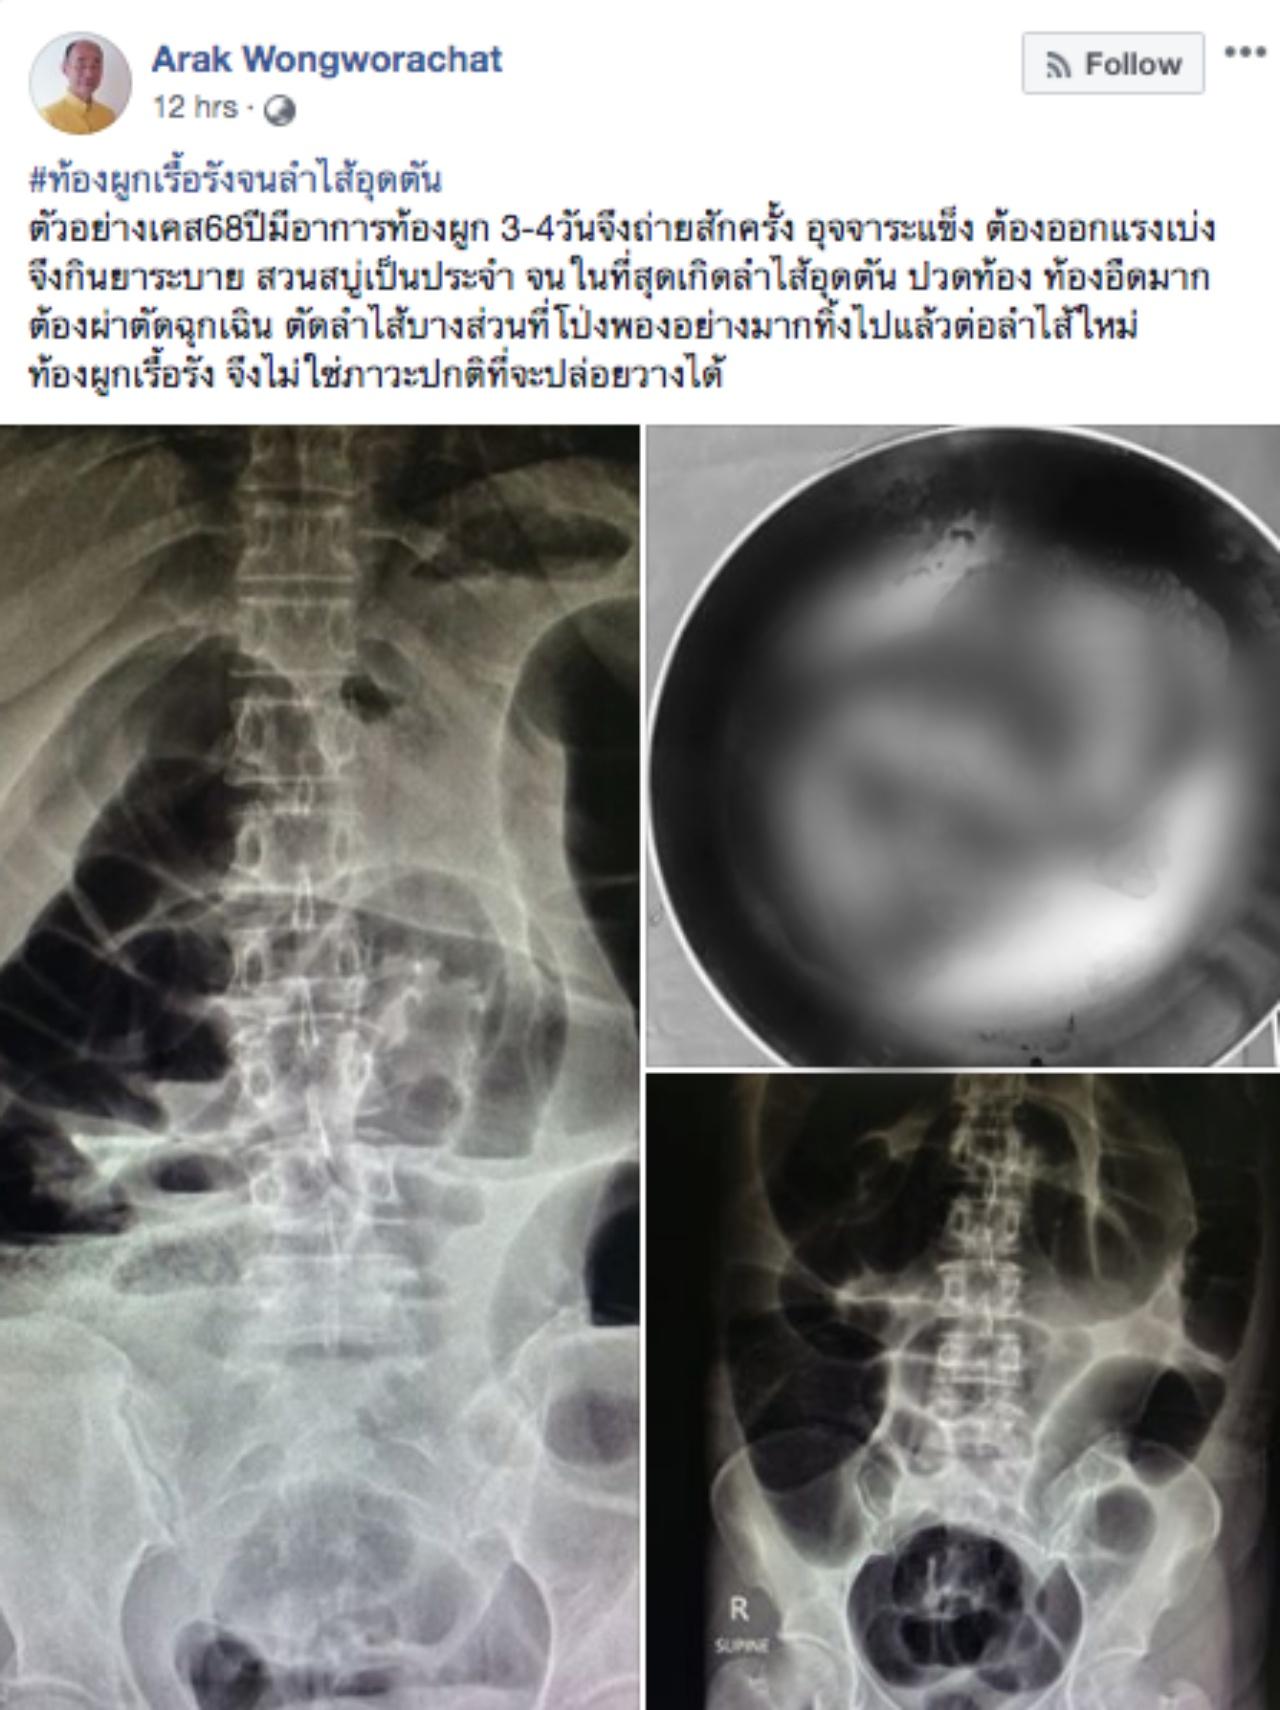

หมออารักษ์ เล่าเคสคนไข้วัย 68 ปี ท้องผูกเรื้อรัง กินยาระบาย สวนสบู่เป็นประจำ สุดท้ายลำไส้อุดตัดต้องผ่าตัดต่อลำไส้ใหม่

วันที่ 18 ส.ค.62 นพ.อารักษ์ วงศ์วรชาติ ผู้อำนวยการโรงพยาบาลสิชล จ.นครศรีธรรมราช โพสต์ภาพและข้อความเตือนภัยกรณีท้องผูกเรื้อรังจนลำไส้อุดตัน โดยยกตัวอย่าง คนไข้อายุ 68 ปี มีอาการท้องผูก 3-4 วันจึงจะขับถ่าย อุจจาระแข็ง กินยาระบาย มีการสวนสบู่เป็นประจำ

จนในที่สุดลำไส้เกิดอุดตัน มีอาการท้องอืด ท้องอืดมาก ต้องเข้ารับการผ่าตัดฉุกเฉินตัดลำไส้บางส่วนที่โป่งพองอย่างมากทิ้งไป แล้วต่อลำไส้ใหม่ "ท้องผูกเรื้อรัง จึงไม่ใช่ภาวะปกติที่ปล่อยวางได้".